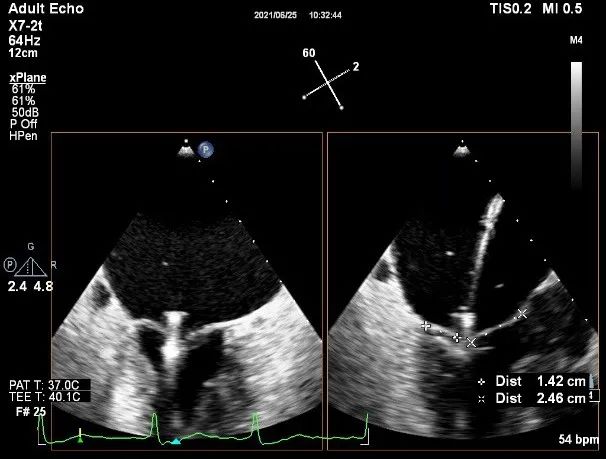

术中超声

确定房间隔穿刺点:靠后

2D视图下测量大鞘长度2cm

3D视图打开夹子

X-plane:下第夹子尝试捕获2区

X-plane:测量前叶长25mm,后叶长14.2mm

X-plane:计算前叶捕获长度8mm,后叶捕获长度7mm

3D视图下观察二尖瓣双孔形态

3D-color:残余少量返流